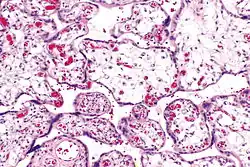

Micrograph of villous immaturity. H&E stain.

Placental villous immaturity is chorionic villous development that is inappropriate for the gestational age.

Immature chorionic villi are larger and have more central blood vessels; thus, the diffusion distance for gas and nutrient exchange is larger and, therefore, placental function is impaired.